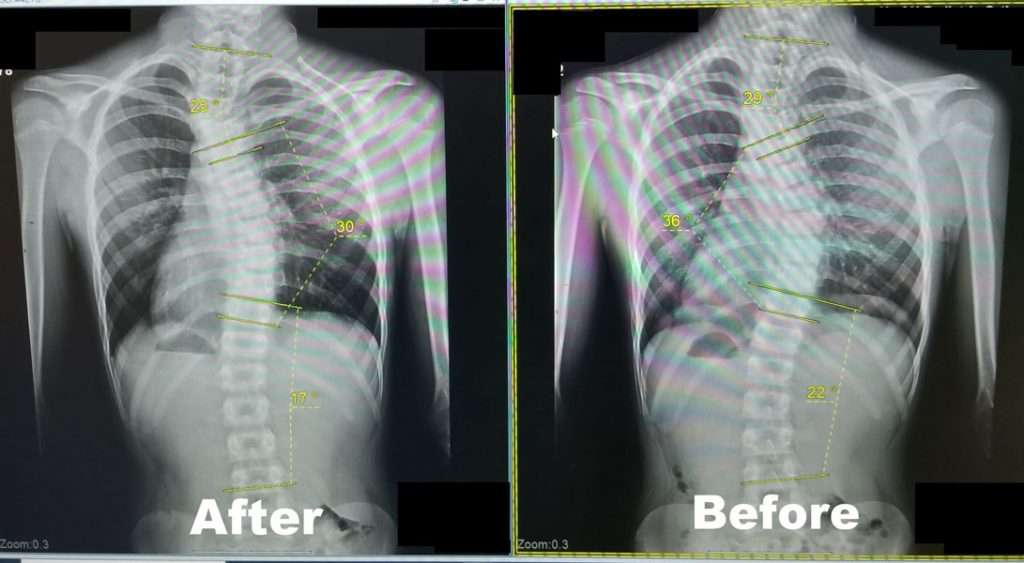

Scoliosis is measured on x-ray as a Cobb Angle. This measurement tells us how bad the scoliosis is and then guides us in how we treat it. Curves under 10 degrees usually aren’t considered scoliosis. Those curves 10-25 are called mild curves and we treat them with scoliosis specific exercise. Curves 25-45 degrees are treated with scoliosis specific exercise and bracing. Those above 45 degrees are usually surgical candidates. There is a measurement error of 3-5 degrees, which means to really have significant change, it needs to be above that.

Here are some examples of what can be done with scoliosis specific exercise with a variety of patients. The main goal of treatment is to STOP progression of the curve. With hard work and dedication we can also see reduction in the curve.